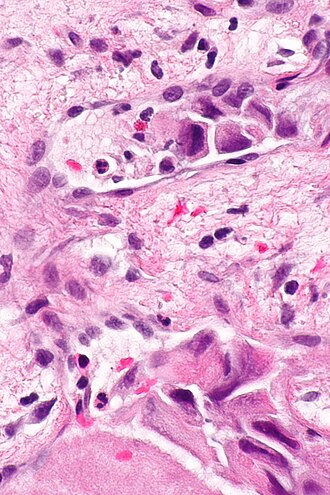

Small focus of LVI in a merkel cell carcinoma. (WC/Nephron)